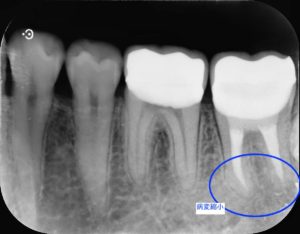

根管治療終了後3ヶ月

根管治療終了後1年

左下第二大臼歯部に不良補綴物をみとめたため、レントゲン検査を行うと根尖部透過像がみられた。根管内に破折器具がみられたため、破折器具の除去および根管内の感染除去を行った。経過観察後、根尖部透過像の縮小をみとめたため、歯冠修復を行った。

今回の症例では根管内の汚染が強く、破折器具もはじめからしっかり見えたことから超音波切削器具と次亜塩素酸ナトリウム等を用いて除去しました。再度根管充填を行ったあと、病変の縮小をみとめた後に歯冠修復を行いました。